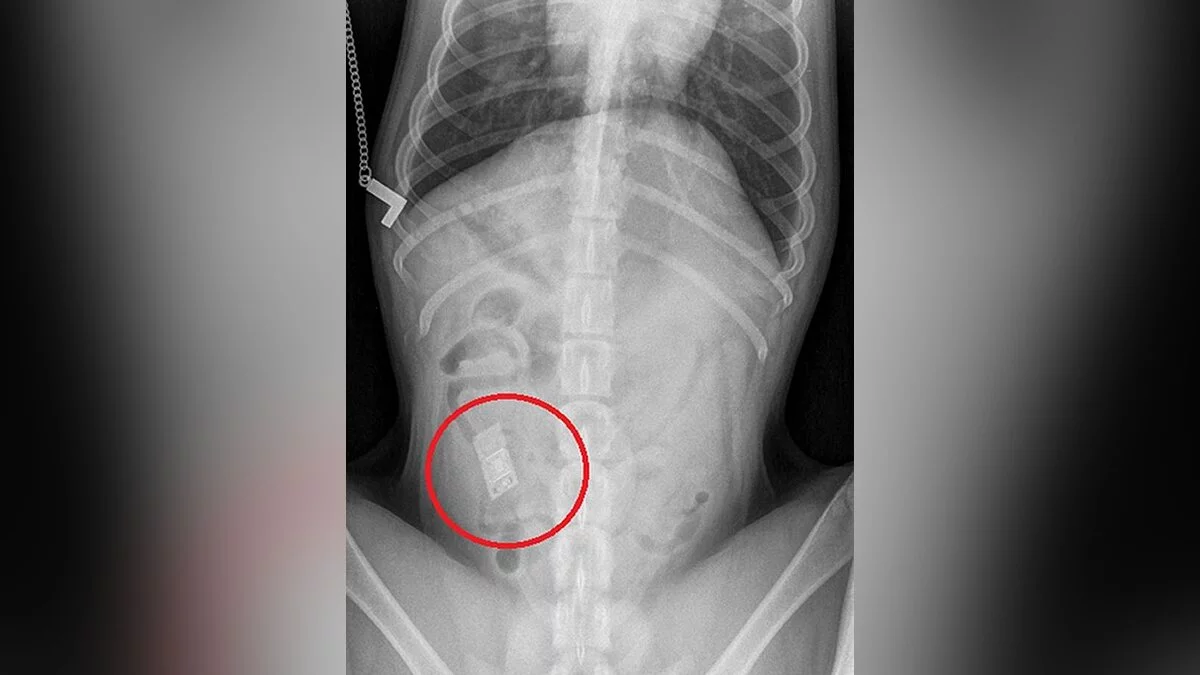

Собаку отвезли в диспансер для больных животных, где ветеринары сделали ей рентгенограмму желудка. На снимке они увидели сторонний предмет, застрявший в кишечнике животного. Оказалось, что это игровой картридж от Nintendo DS. Самое примечательное, что у хозяев нет дома видеоигр и консоли.